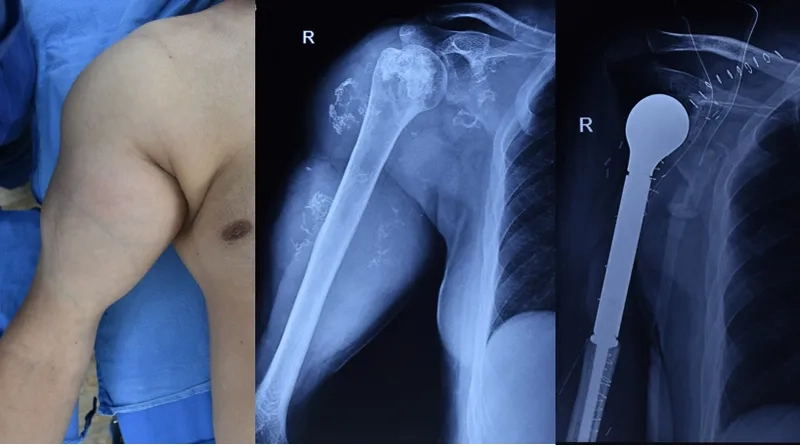

• Sarcoma treatment is complex and often involves a combination of surgery to remove the tumor, radiation therapy, and chemotherapy.

Image of a soft tissue sarcoma